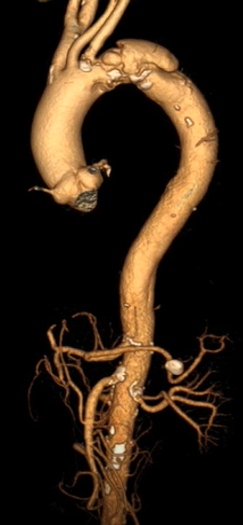

★ 病例2:模块内嵌分支胸主动脉覆膜支架系统

术前

术后